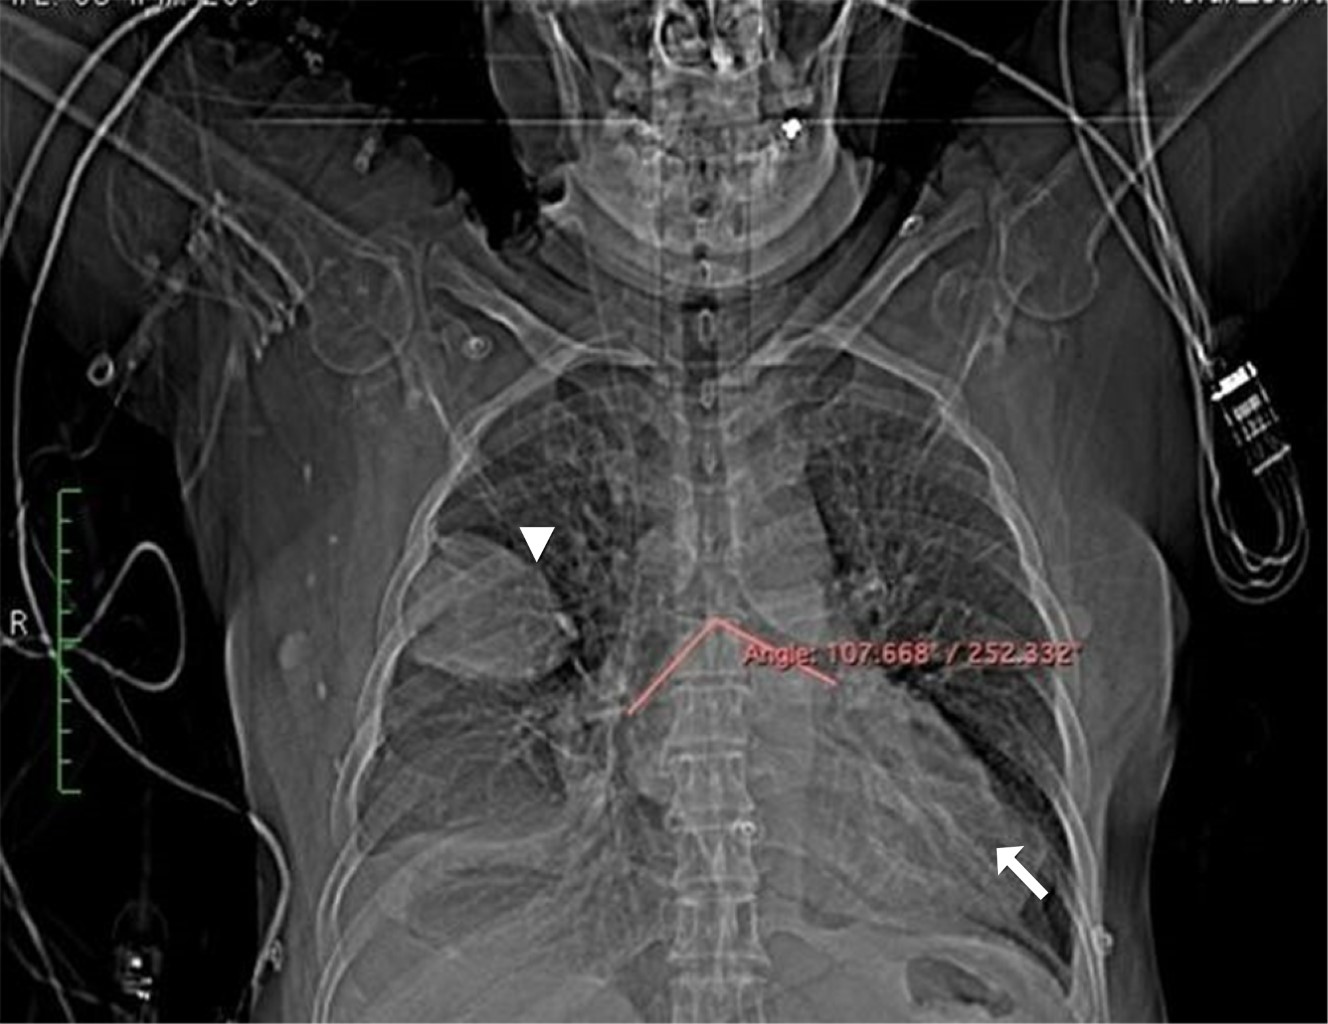

A la exploración física con peso 69 kg y talla 163 cm, despierta, tranquila, cooperadora, buena coloración mucotegumentaria, cráneo normocéfalo, ojos simétricos con pupilas isocóricas, normorreflécticas, mucosa oral húmeda, anodoncia parcial; cuello cilíndrico, tráquea central, móvil; tórax normolíneo, buena amplexión y amplexación, ruidos respiratorios normales no sibilancias ni estertores, ruidos cardíacos rítmicos adecuada intensidad, abdomen semigloboso por panículo adiposo, blando, depresible, no doloroso, extremidades con leve edema en miembros inferiores, simétricas, pulsos distales presentes, normales, llenado capilar menor a tres segundos. El electrocardiograma mostró ritmo sinusal, necrosis en cara inferior, resto normal. El ecocardiograma reportó cardiopatía isquémica, dilatación ligera de sus diámetros, geometría conservada, movilidad global y segmentaria del VI en reposo y sin maniobras inductoras de isquemia con acinesia lateral apical y anterolateral mediobasal con espesor limítrofe e hiperrefringencia, sitio en donde se visualiza solución de continuidad a nivel del miocardio ventricular con cociente menor de 0.5, flujo bidireccional con expansión sistólica correspondiente a imagen de pseudoaneurisma ventricular, fracción de eyección del ventrículo izquierdo de 40%, presión sistólica de la pulmonar de 42 mmHg, media normal resistencia vascular periférica (RVP) menor de tres unidades Wood. La coronariografía mostró circunfleja lesión de 80% antes de la bifurcación con la obtusa marginal, la cual tiene lesiones en todo su trayecto de 80% en tándem, arteria menor de 2 mm, además de hipocinesia generalizada y dilatación ventricular importante, resto sin lesiones angiográficas. La tomografía de tórax mostró dilatación aneurismática de la pared externa del ventrículo izquierdo de 60.6 × 78.7 mm de diámetro transverso y anteroposterior respectivamente y en su parte latero-superior parece advertirse un pequeño punto de fuga hacia cavidad pericárdica, sin evidencia de extensión hasta cavidad pericárdica (Figuras 1, 2 y 3).

Figura 1

Figura 2

Figura 3